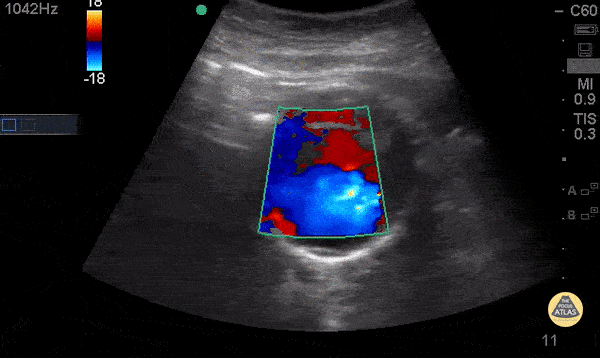

Aorta - Mural Thrombus in AAA - Doppler

74 y/o F hx stage 4 lung cancer, AAA, presented with chest pain and SOB x 1 day. POCUS shows the aorta is larger than the normal diameter of 3 cm, representing an abdominal aortic aneurysm, and measuring approximately 5.6 cm at its largest point. On cross section you are able to see a large mural thrombus with decreased diameter of blood flow through the center. Juliana Jaramillo MD - Kings County Emergency Medicine